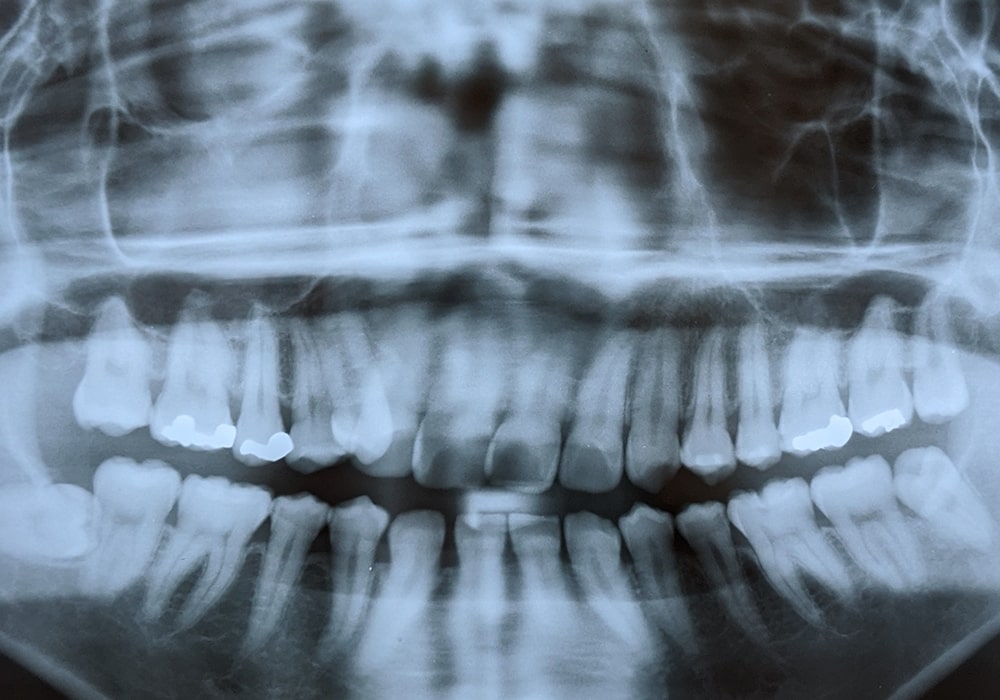

レントゲンや歯科用CTを使って、現在の歯並びやかみ合わせを確認します。また、歯の型取り、口腔内写真の撮影、お顔の正面と横顔の写真撮影などを行い、必要なデータを収集します。